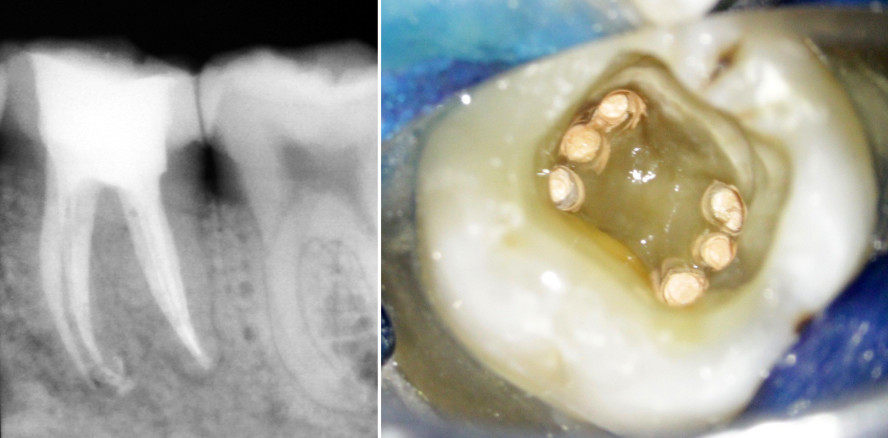

Bei Revisionen von Misserfolgen endodontischer Therapien fanden wir in oberen Molaren immer mindestens ein unbehandeltes Kanalsystem. Zweifellos...

Bei Revisionen von Misserfolgen endodontischer Therapien fanden wir in oberen Molaren immer...

Die genaue Kenntnis der Kanalanatomie sollte die Ausgangsbasis einer endodontischen Behandlung sein. Im beschriebenen Fall ist es die ungewöhnliche...

Die genaue Kenntnis der Kanalanatomie sollte die Ausgangsbasis einer endodontischen Behandlung...